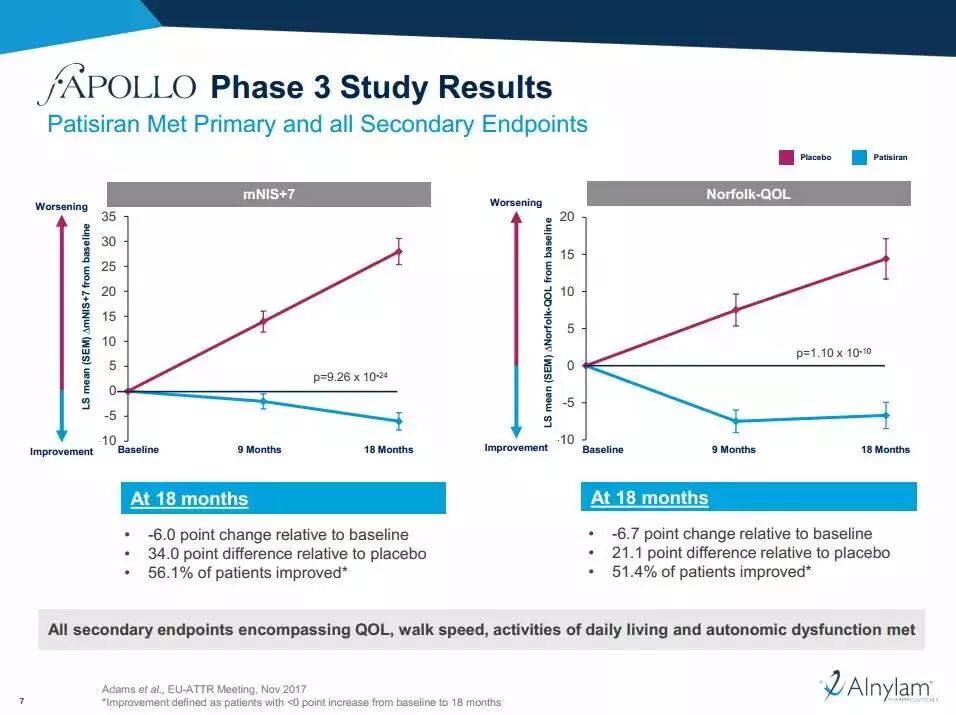

• 临床突破:2018年8月11日,FDA批准由Alnylam研发的patisiran上市,这是首款RNAi疗法,用于治疗一种致命的罕见病称为hATTR淀粉样变性。patisiran能抑制特定mRNA的表达,清除组织里的淀粉样蛋白沉积,恢复组织功能。

• 试验研究:该疗法的3期临床试验结果如上,在18个月时,与安慰剂相比patisiran显著减少了患者的神经学病变。